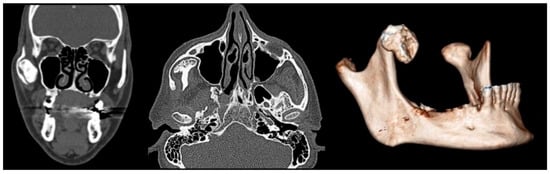

| 3 | Male | 34 | Myositis ossificans traumatica | CT | 15 mm | Excision of calcified mass | 52 mm |

| 4 | Male | 44 | Chronic osteomyelitis of the mandible |

OPG CT/MRI | 13 mm | Incision and drainage of the abscess and surgical curettage | 48 mm |